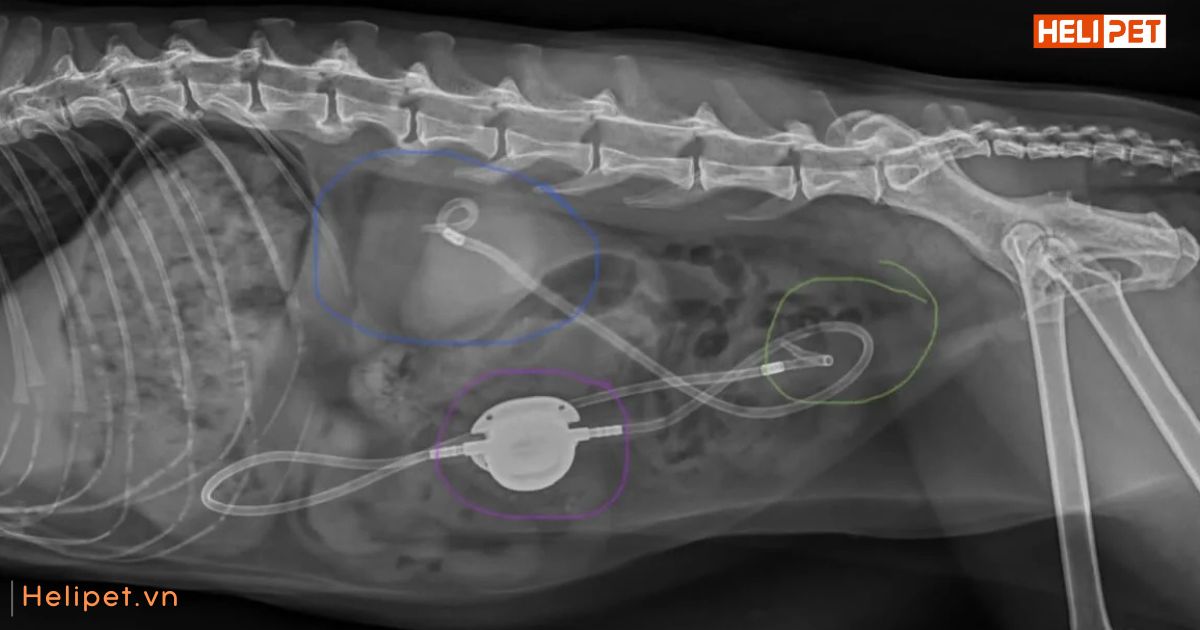

Hình ảnh chụp X-quang mèo bị bệnh sỏi thận

Chụp X-quang hoặc siêu âm: Xác định kích thước, vị trí và loại sỏi thận.